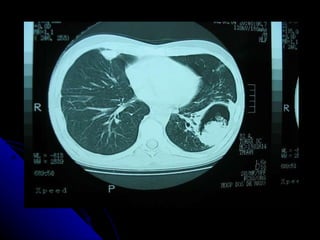

DIAGNÓSTICO POR IMÁGENES DEL TÓRAX Examen radioscópico Examen radiográfico Foto roentgen US torácica – US endobronquial. TAC tórax TACAR. Tomografía emisión positrones Tomografía helicoidal multicorte. RMN tórax.

SÍNDROME PARENQUIMAL Conjunto de signos radiográficos que traducen una lesión en el parénquima pulmonar, la  que  puede ser localizada o difusa. Didácticamente podemos dividirlo en tres tipos: Alveolar Intersticial Mixto ( alveolo intersticial)